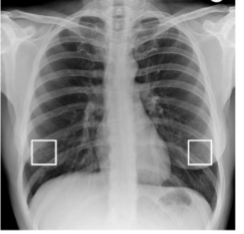

Identify soft tissues/what are you looking for?

nipples

identify nipple shadows

yes